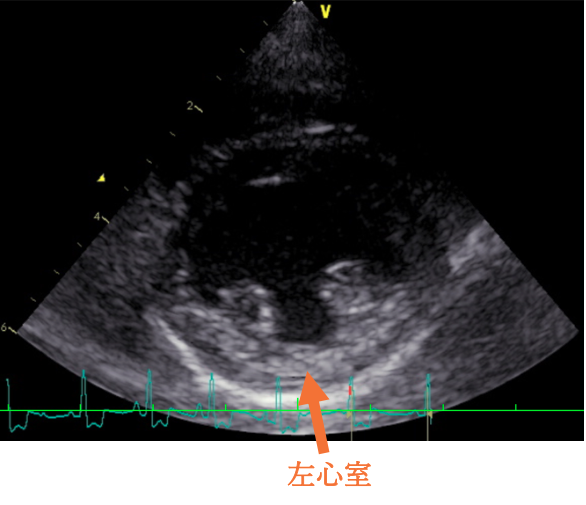

<心臓超音波検査結果>

今回の⼼臓超⾳波検査では、僧帽弁からの⾎液の逆流は認められるものの、⼼臓のサイズの拡⼤や負荷の増加は認められませんでした。そのため、現在の治療(強⼼薬・⾎管拡張薬など)を継続しながら経過観察となりました。

わんちゃんの⼼臓は、右⼼房/右⼼室・左⼼房/左⼼室という 4 つの部屋からできています。それぞれの間には⾎液が逆流しないように「弁」があります。そのうち、左⼼房と左⼼室を隔てているのが「僧帽弁」です。